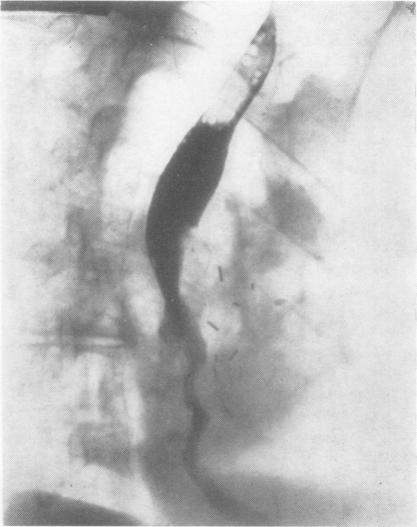

SMITHERS D W

Thorax. 1956 Dec;11(4):257-67. doi: 10.1136/thx.11.4.257.